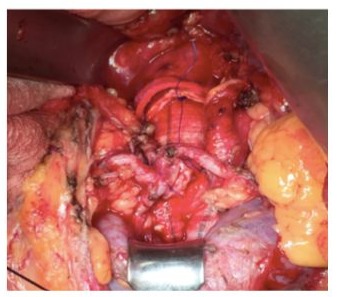

Figure 1: Renal Perfusion with Custudiol.

Figure 2: Renal Arteries Reimplantation